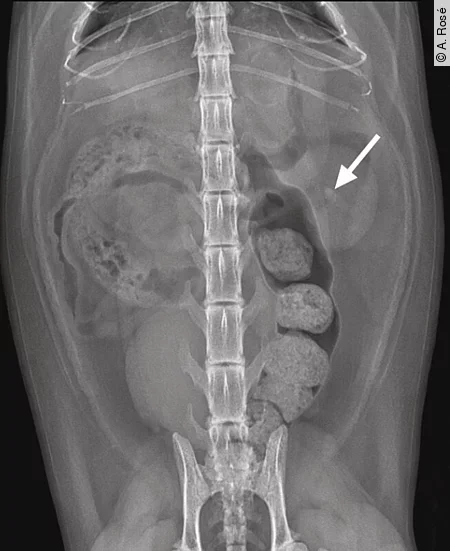

Bildgebende Verfahren wie Abdomen Ultraschall und Röntgen sind unerlässlich, um strukturelle Veränderungen (z. B. Zysten, Neoplasien) zu erkennen und Komplikationen wie Hydronephrose oder Uretersteine zu identifizieren [Abb. 1] und [2]. Weitere spezifische Untersuchungen (z. B. T4, PTH-Bestimmung, SDMA) können je nach klinischem Verdacht ergänzend sinnvoll sein [Tab. 1] und [2].